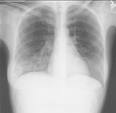

透明肺 不是單一疾病。凡在標準條件 X射線檢查時病側肺較正常側透過 X射線量多而顯示肺含氣量增加,透亮,在 X射線胸片上呈顯著黑暗部分,均可廣泛稱之為透明肺。慢性氣管炎致成的阻塞性肺氣腫,一葉或一側肺因腫瘤、異物、氣管的嚴重炎症等,致使支氣管梗阻,或因外壓性疾病(腫瘤、腫大淋巴結)致成的支氣管阻塞,因吸氣易呼氣難,致使肺泡含氣量增加,發生限局性肺氣腫也可呈透明肺。先天性或新生兒肺葉肺氣腫,特發性一葉或一側肺氣腫,均呈現病肺透明度增加,亦可統稱為透明肺。

診斷和治療 X射線檢查是重要診斷方法,如對肺氣腫、肺大泡、囊腫、肺部腫瘤等多可明確診斷。對肺不發育、發育不全、動靜脈瘺及肺動靜脈血管畸形等需作血管造影和氣管造影確診。治療除對症外(如控制肺部感染、氧氣治療),有的需手術治療,如致成透明肺的肺大泡、腫瘤均需手術切除,肺隔離症、囊腫、反覆繼發感染、咯血、單發的動靜脈瘺均是手術切除的指征